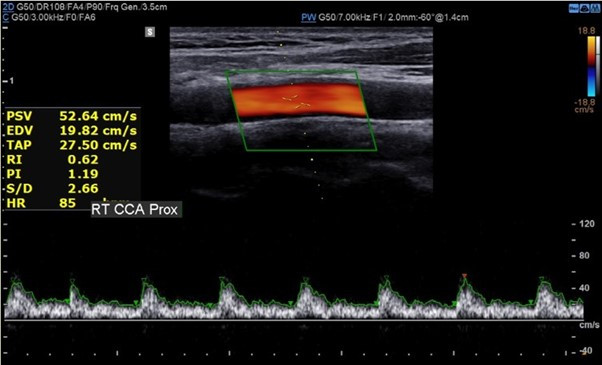

그림14.jpg 촬영 일시: 2025.04.29

<Fig 1. 경동맥초음파 영상>

역시나... 후두신경 주변으로 염증 반응이 있더라고요.

환자분께 화면을 보여드리면서 설명해드렸어요.

"여기 보세요. 이 부분이 붓고 염증이 있죠?

이게 바로 통증의 원인입니다"